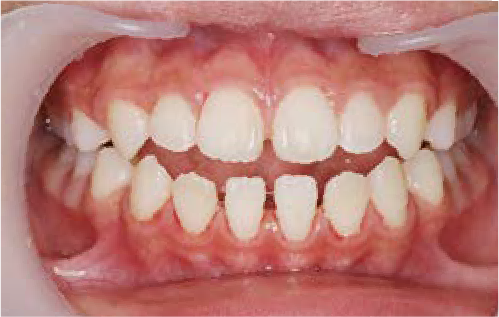

ガタガタな歯並びに悩むも…抜かずに治す選択

Kさん (矯正開始時:8歳)

Before

After

前歯のすき間や歯並びの乱れが見られ、普段の生活の中で、無意識に舌を押しつけるクセや飲み込み方のクセが確認されました。

治療を終えて

装置をしっかり使うことで、あごの位置が整い、舌の正しい位置や動きが戻り、ほっぺたやくちびるの筋肉の使い方も改善されました。その結果、歯並びが整いお口の機能も良くなりました。もちろん非抜歯での治療です。

主訴・治療内容 他院で抜歯のうえ、ブラケット矯正を勧められたが、できれば歯を抜かずに治療したいとの要望で来院されました。

治療期間 5年4ヶ月

費用 495,000円(税込)